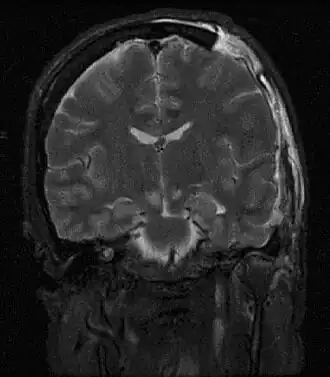

| Imagem por ressonância magnética de lesões causadas por uma hérnia cerebral | |

Hérnia cerebral é um efeito secundário potencialmente mortal de pressão intracraniana muito elevada, que ocorre quando parte do cérebro é pressionada contra as estruturas do crânio. O cérebro pode atravessar estas estruturas, como o falx cerebri, o tentorium cerebelli e até mesmo o foramen magnum (o orifício na base do cérebro pelo qual a espinal medula se liga ao cérebro).[1] Em muitos casos a hérnia cerebral apresenta-se com postura anormal, indicativa de lesões no cérebro.[2] Pode também ocorrer alteração do estado de consciência, com Escala de coma de Glasgow entre 3 e 5.[2] As pupilas podem-se apresentar dilatadas e não reagir à luz.[2]

O tratamento consiste na remoção cirúrgica da massa etiológica e craniectomia descompressiva. Uma hérnia cerebral pode causar deficiência grave ou morte. Quando a hérnia é visível numa TAC, o prognóstico neurológico é geralmente desfavorável.[2]